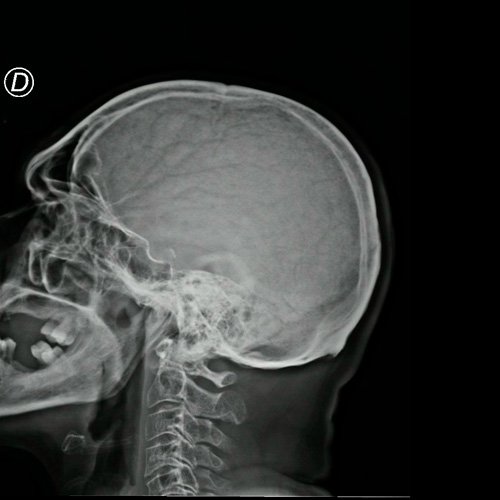

- Radiografía de cráneo (Día 11): no se observan lesiones osteolíticas.